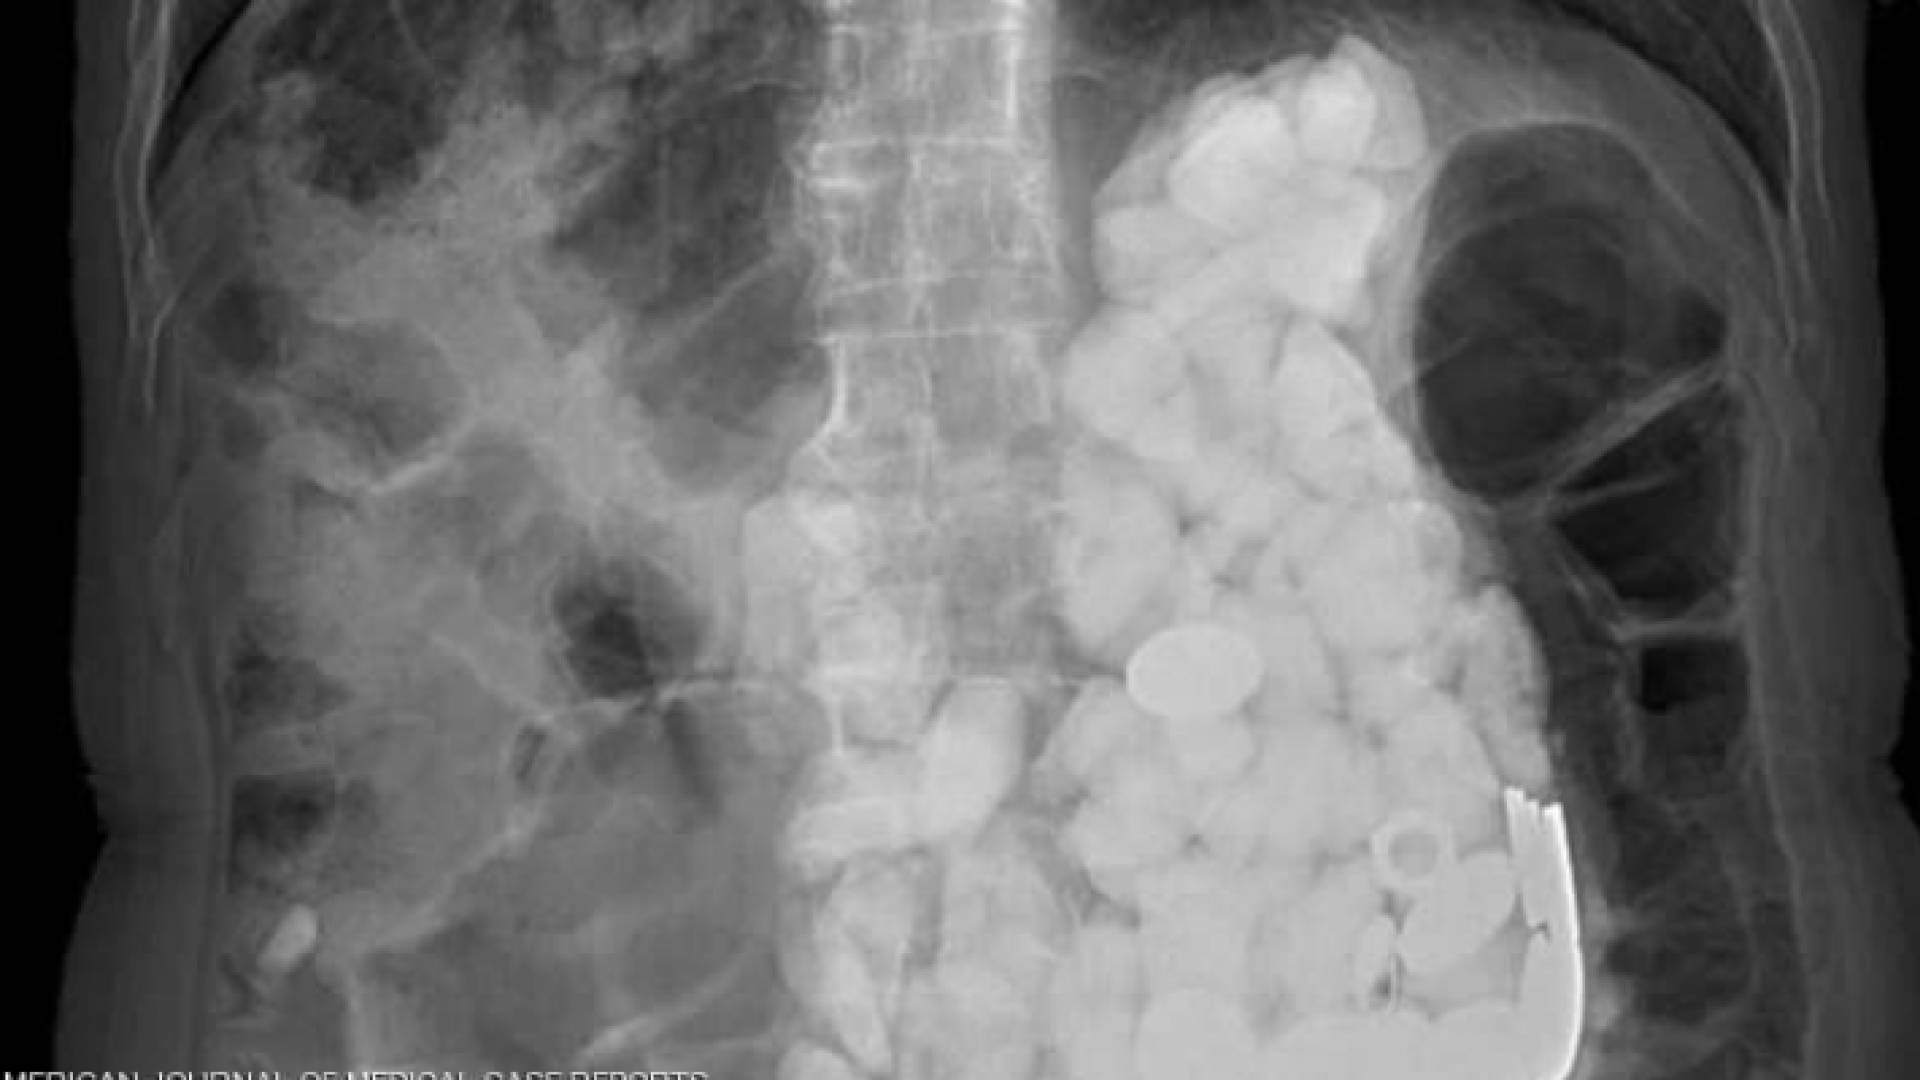

وأجرى أطباء بمستشفى Ilsan Paik بجامعة إنجي الكورية الجنوبية، مجموعة من الفحوصات لمعرفة السبب الكامن وراء هذه الأعراض، حيث شعروا بشيء يشبه الحجارة عند لمس بطنه، واكتشفوا تراكم أجسام في المعدة كلها يصل وزنها إلى كيلوغرامين.

ولم تفلح محاولات الأطباء في إخراج الأجسام من معدة الرجل الذي ولد بإعاقة ذهنية، باستخدام طريقة المنظار نظرا لكثرتها، مما دفعهم للحل الجراحي.